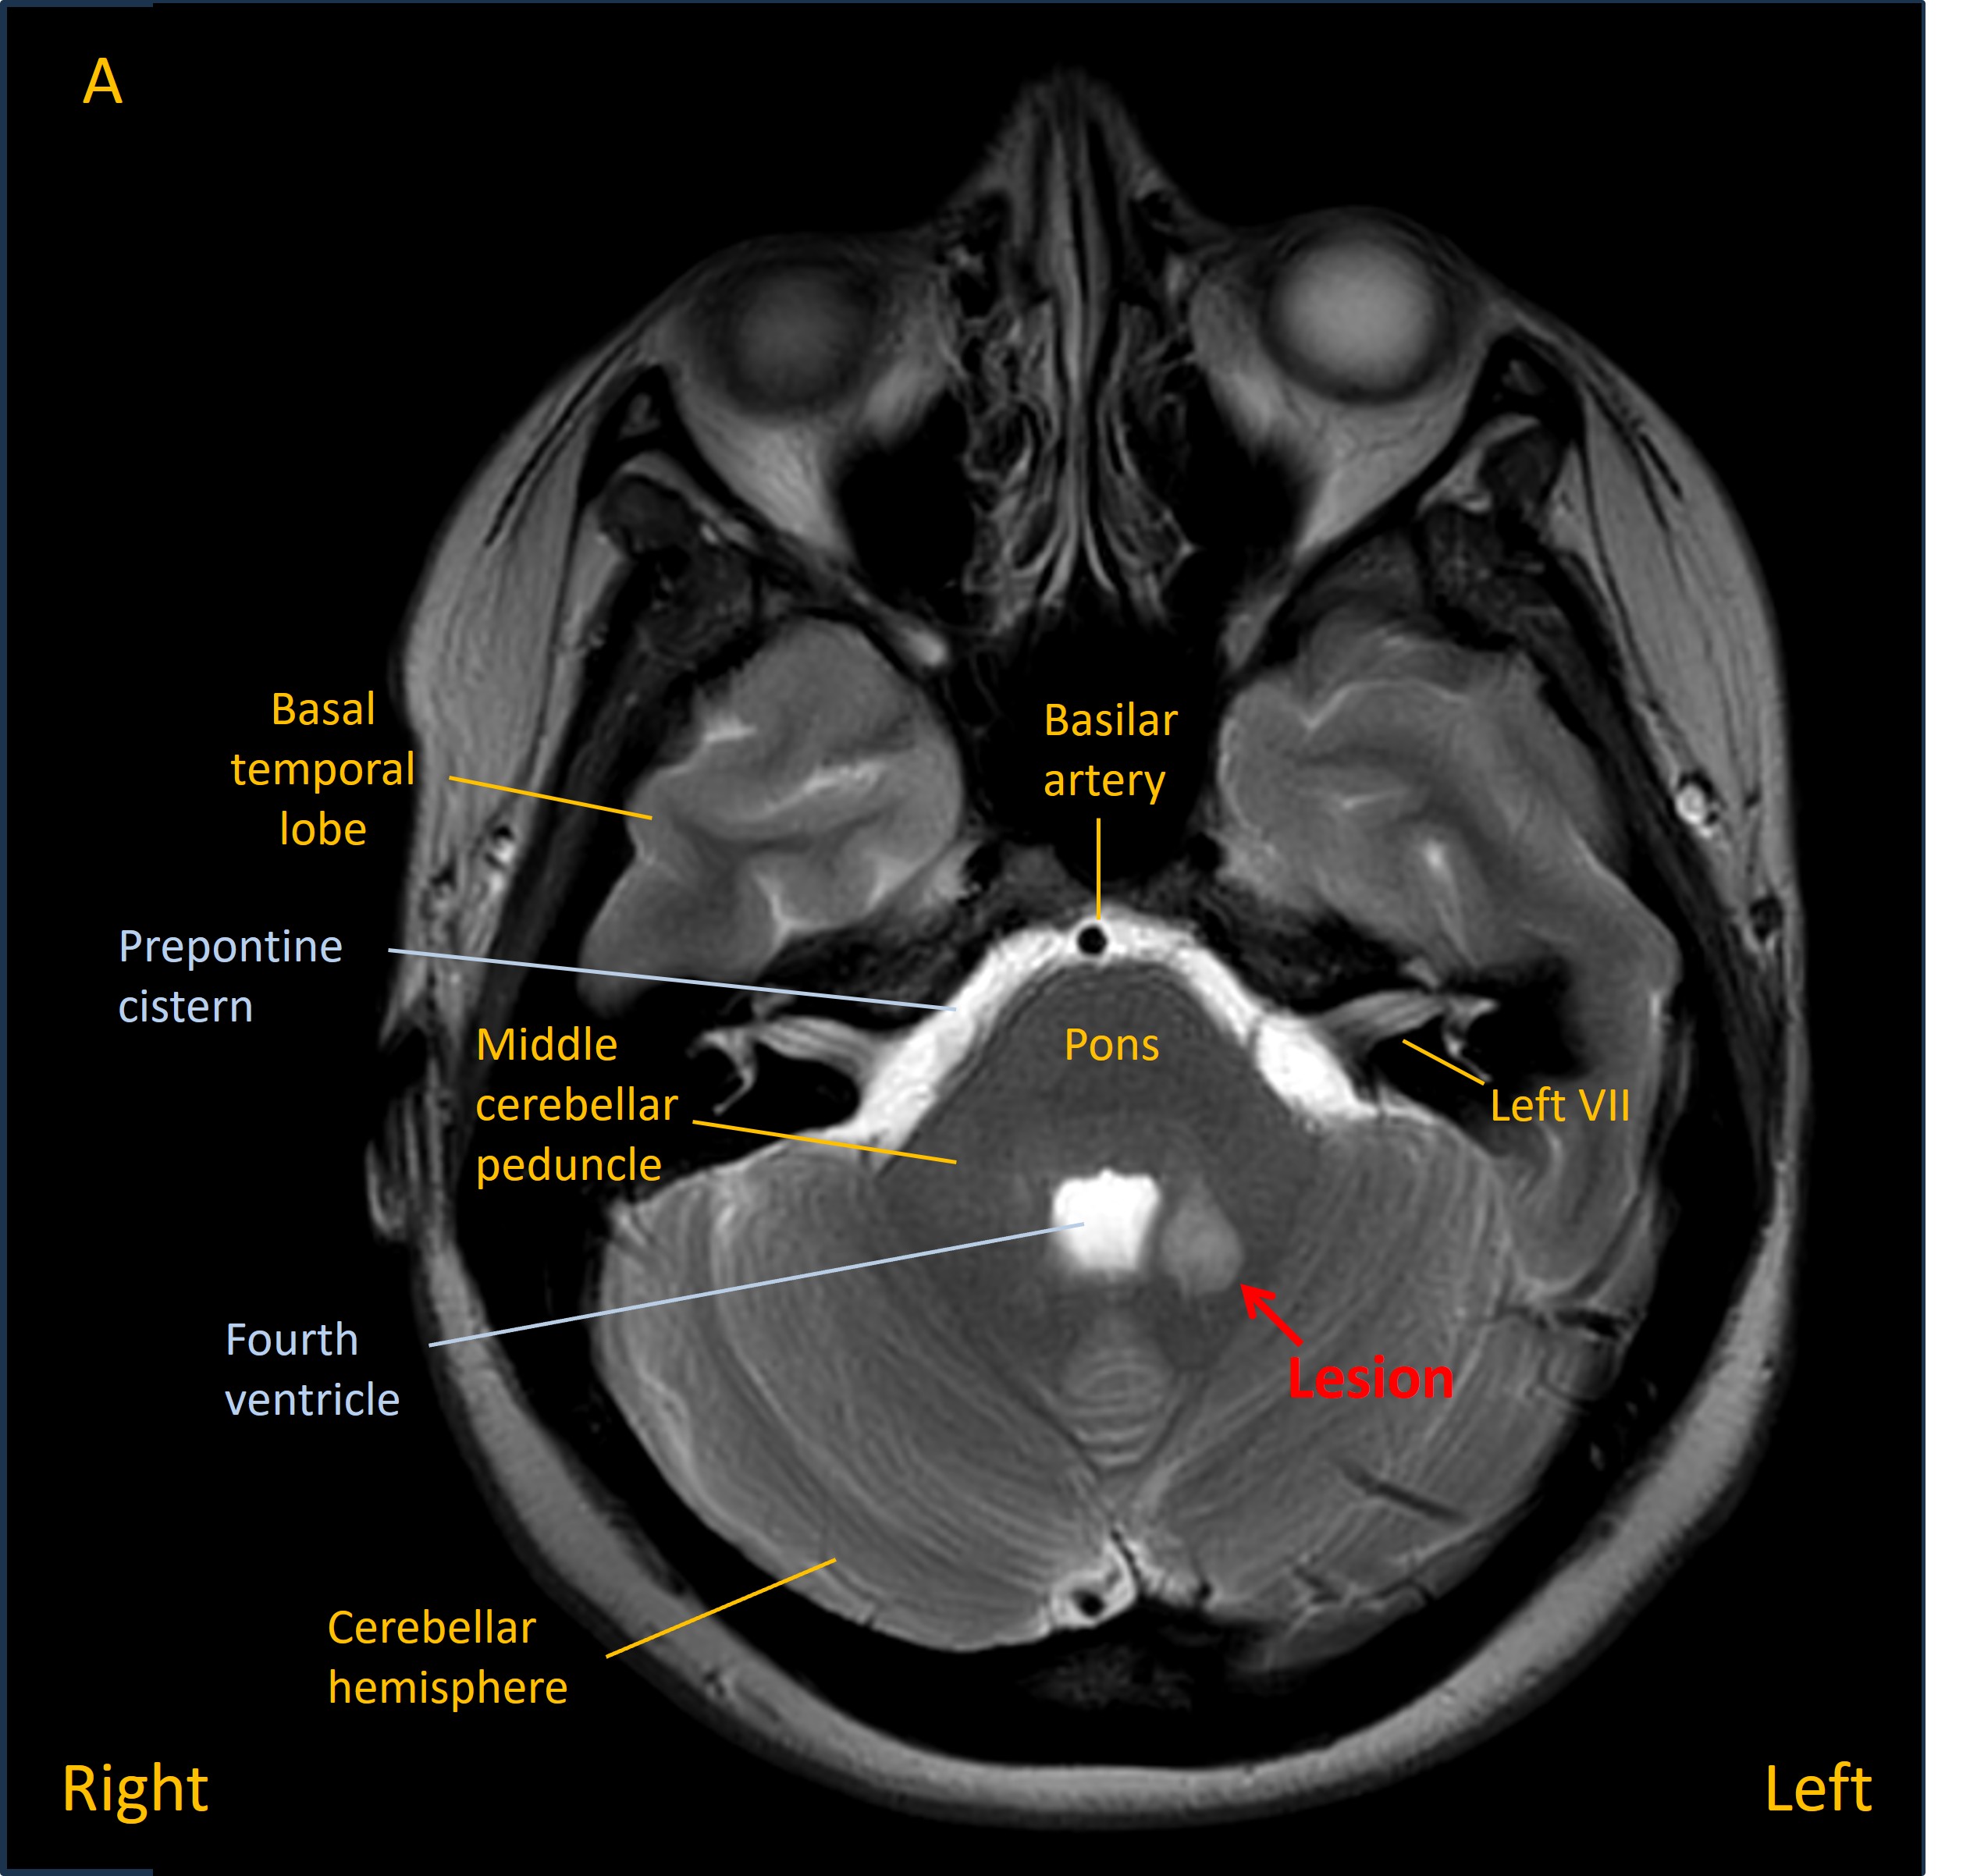

She was admitted and had an MRI brain which showed a lesion in the left middle cerebellar peduncle adjacent to the fourth ventricle. Imaging features suggested a solitary demyelinating lesion – and in the absence of other lesions, or prior symptoms, this was not in keeping with a diagnosis of multiple sclerosis (MS).